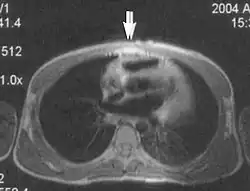

Metal artifacts occur at interfaces of tissues with different magnetic susceptibilities, which cause local magnetic fields to distort the external magnetic field. This distortion changes the precession frequency in the tissue leading to spatial mismapping of information. The degree of distortion depends on the type of metal (stainless steel having a greater distorting effect than titanium alloy), the type of interface (most striking effect at soft tissue-metal interfaces), pulse sequence and imaging parameters. Metal artifacts are caused by external ferromagnetics such as cobalt containing make-up, internal ferromagnetics such as surgical clips, spinal hardware and other orthopaedic devices, and in some cases, metallic objects swallowed by people with pica.[3] Manifestation of these artifacts is variable, including total signal loss, peripheral high signal and image distortion (Figs 3 and 4).[1] Reduction of these artifacts can be attempted by orientating the long axis of an implant or device parallel to the long axis of the external magnetic field, possible with mobile extremity imaging and an open magnet. Further methods used are choosing the appropriate frequency encoding direction, since metal artifacts are most pronounced in this direction, using smaller voxel sizes, fast imaging sequences, increased readout bandwidth and avoiding gradient-echo imaging when metal is present. A technique called MARS (metal artifact reduction sequence) applies an additional gradient, along the slice select gradient at the time the frequency encoding gradient is applied.